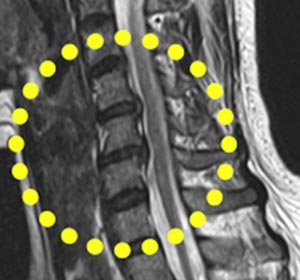

이런 변화를 ‘노화(퇴행성 변환)’라고 하는데, 노화는 누구에게나 나타나고 자세나 일상생활의 활동량에 따라 좀 더 민첩하게 진행될 수 있습니다. 디스크가 노화를 해결할 수 없을 크기가 되면 디스크가 돌출되는 증상이 일어나요. 디스크가너무하게 나오면 신경이 마비될 수 있겠지만 일부 환자에서 그렇고, 대개 은 목 뒤의 통증(경부통), 어깨의 통증(견갑통), 두통 등의 증상이 나타난다고 하고 이런 증상들이 목 디스크의 초기 증상일 수 있습니다.

목은 목뼈(경추) 7개로 되어 있다며 뼈와 뼈 사이에 디스크가 있습니다. 디스크는 기립 자세에서 수직으로 끼치는 압력을 분산하고 목이 동작할 때 관절 역할을 합니다. 나이가 들면 아무라도 피부 탄력이 감퇴하여 주름이 생기듯 척추의 디스크도 수분 함유하고 있는 분량이 쇠퇴하여 긴장되고 이로 인하여 충격을 섭식하고 압력을 분산시켜서하는 기능이 저하되요.